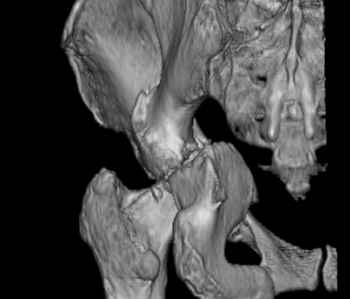

Уважаемые коллеги, возник вопрос по лечению нашей пациентки 60 лет. Около года назад множественная травма: в том числе Т-образный перелом вертлужной впадины. На сегодняшний день сращение отломков имеется на ограниченных участках, имеется дефект задней колонны вертлужной впадины. Движения неплохие, ходит с костылями, приступая на ногу. По мнению эдопротезистов при установке антипротрузионного кольца или октопуса не хватит костного материала и необходимо перед протезированием выполнить реконструкцию впадины, иначе чашка протеза неминуемо выпадет.Просьбы поделиться положительным и отрицательным опытом протезирования в подобных случаях.Возможно ли обойтись без реконструкции?Или лучше с ней?С уважением РАВ.

По моему мнению предварительну реконструкцию делать нет необходимости. Операцию надо выполнять одномоментно с пластикой вертлужной впадины. по поводу того, что не хватит головки. Да не исключено. Но ведь есть и другие материалы. Лучше при таком раскладе иметь в запасе замороженную головку. если нет возможности, как вариант два крыла подвздоной кости + хронос или его аналоги. По поводу выбора конструкции. Октопус в данной ситуации будет совсем не уместен, т.к. имеется дефект задней колонны вертлужной впадины. Да как конструкция октопус встанет не плохо. Но в функциональном плане не будет хорошей задне латерально и заднемедиальной точек опры впадины на период перестройки трансплатов. И по этому в данной ситуации более уместно кольцо Бурх(г)-Шнайдера с аналогичной пластикой, но возможнотью зафиксировать отломки задней колонны, крыши. Естественно цементная чашка с козырьком из кросс линк полиэтилена. Гололвка керамика, ножка бесцементная можно Цваймюллера или любой другой конструкции, они сейчас все хороши.

Основное внимание необходимо уделить стабильности костных фрагментов в зоне перелома вертлужной впадины. Если имеется нестабильность я предпочел бы Октопус для остеосинтеза и стабильности вертлужной впадины. Этот момент является основным для успешного протезирования.